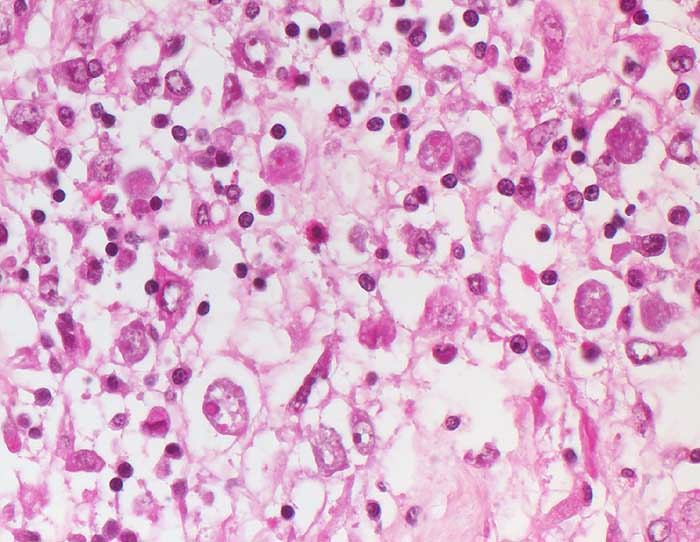

Rundliche gewebsinvasive Magnaform von Entamoeba histolytica mit rundem Kern und phagozytierten Erythrozyten im Gewebe am Rand des Ulkus.

Die gewebsinvasiven Throphozoiten bewirken an der Schleimhautbasis eine Histolyse an der Grenze zur Muscularis mucosae unter Ablösung der Schleimhaut. Bei 90-99% der Infizierten verläuft der Infekt asymptomatisch (intestinale Darmlumeninfektion mit Erregerausscheidung). Die restlichen Patienten leiden an einer invasiven Amöbiasis. Die Krankheit kommt vor allem in den Tropen und Subtropen, seltenerweise aber auch in Mitteleuropa vor. Es gibt ein vegetatives Stadium der Trophozoiten und Zysten, die aus bis zu vier Trophozoiten gebildet werden. Im Dünndarm werden aus ingestierten Zysten Trophozoiten freigesetzt in Form von apathogenen Kommensalen, der Minutaform (12-18 Mikrometer) und der histolytischen Magnaform (bis 20-30 Mikrometer) mit Erythrophagozytose. Die Freisetzung proteolytischer Enzyme bewirkt eine Kolliquationsnekrose. Bei chronischer Ulzeration entwickelt sich ein Amöbom bestehend aus Granulationsgewebe, das den Darm einengen und ein Karzinom imitieren kann. Häufigste Komplikation ist der Leberabszess.